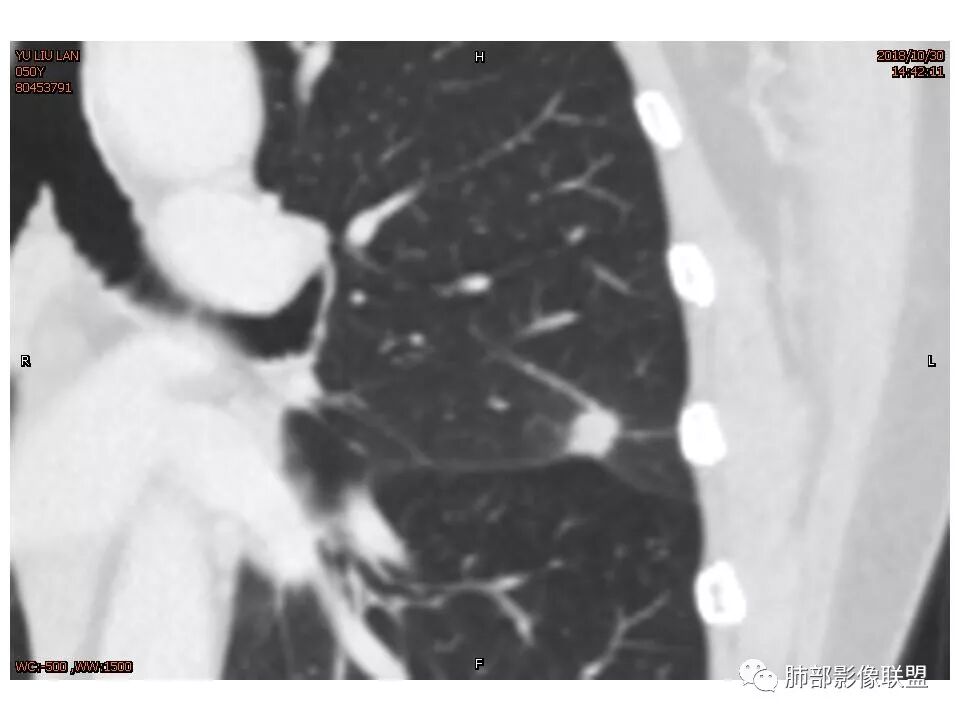

定位左舌,结节,有晕,晕中软毛刺,长毛刺与胸膜牵拉,收缩明显,部分呈方形,明显强化及延迟强化,有支气管近端进入远端阻塞,部分呈鬼脸

鉴别:腺癌 牵拉斜裂,有动静脉相连,

考虑恶性可能性大,毛刺分叶,局部膨隆。收缩明显,牵拉叶间裂

考虑恶性可能性大,毛刺分叶,局部膨隆,牵拉叶间裂收缩明显

因为南大说过实性病变有收缩力往往是慢性炎症。而腺癌毛玻璃才会牵拉叶间裂

轴位像炎性,冠状、矢状位像恶性,真遇到了,纠结

1.胸膜下略不规则实性密度结节影,孤立,缺乏典型深分叶,可见淡薄边界模糊磨玻璃晕,可见相对细长软毛刺。

2.如南边老师分析,病灶缺乏边缘膨隆优势,甚至部分平直内收。

4.综上,病灶更符合炎性,如隐球菌感染等,而不大符合肺腺癌。具体到机化性肺炎略有些出乎预料。